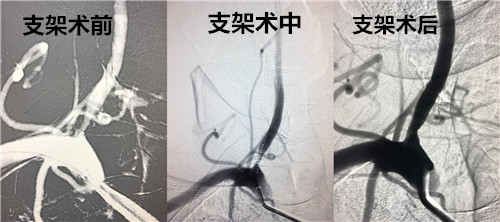

近日,脑血管病治疗中心收治一名右侧椎动脉起始部狭窄患者,对患者实施了陕西省首例TRUMP支架置入治疗椎动脉狭窄。患者以发作性头晕起病,入院后行全脑血管造影提示右侧椎动脉起始部重度狭窄,杨震主治医生团队给予患者行右侧椎动脉狭窄TRUMP支架置入术,术后患者头晕症状消失恢复良好。据悉,此种术式简单,手术风险低,并发症少,目前被认为是椎动脉开口狭窄患者药物治疗无效的一种有效选择。该方法能明确改善血流,缓解狭窄相关的缺血症状,改善预后并预防缺血事件的发生。

据了解,脑血管病治疗中心还完成了渭南地区首例基底动脉狭窄球囊扩张支架置入术。患者因左侧肢体无力、脑干梗塞入院。入院后行全脑血管造影提示右侧基底动脉重度狭窄,给予行基底动脉支架置入术。术后患者病情稳定,恢复良好,左侧肢体肌力较前改善。据悉,基底动脉重度狭窄患者极易发生脑干缺血,病情凶险,自然病程预后差。因此支架置入手术意义重大,受基底动脉血管壁结构及解剖位置影响,基底动脉狭窄球囊扩张支架置入术具有手术风险大、技术要求高、术前准备精细等特点。脑血管病治疗中心实施的此项手术为渭南地区首例。